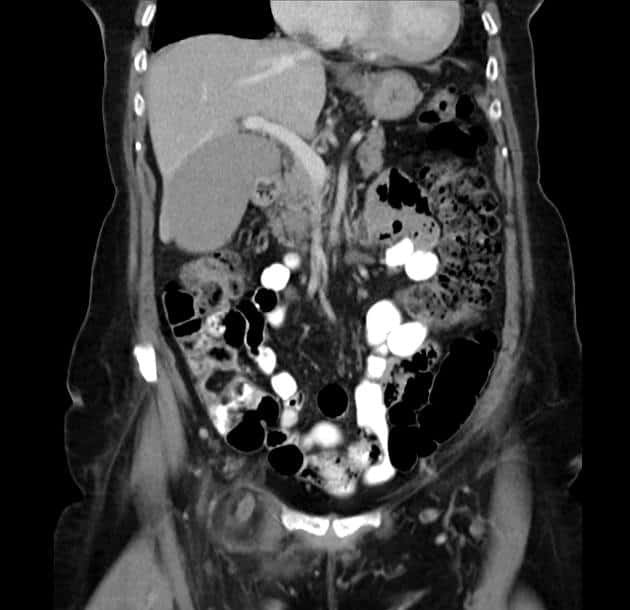

Thoát vị De Garengeot

» Thông tin: Nữ giới – 85 tuổi.

» Lâm sàng: Đau háng phải.